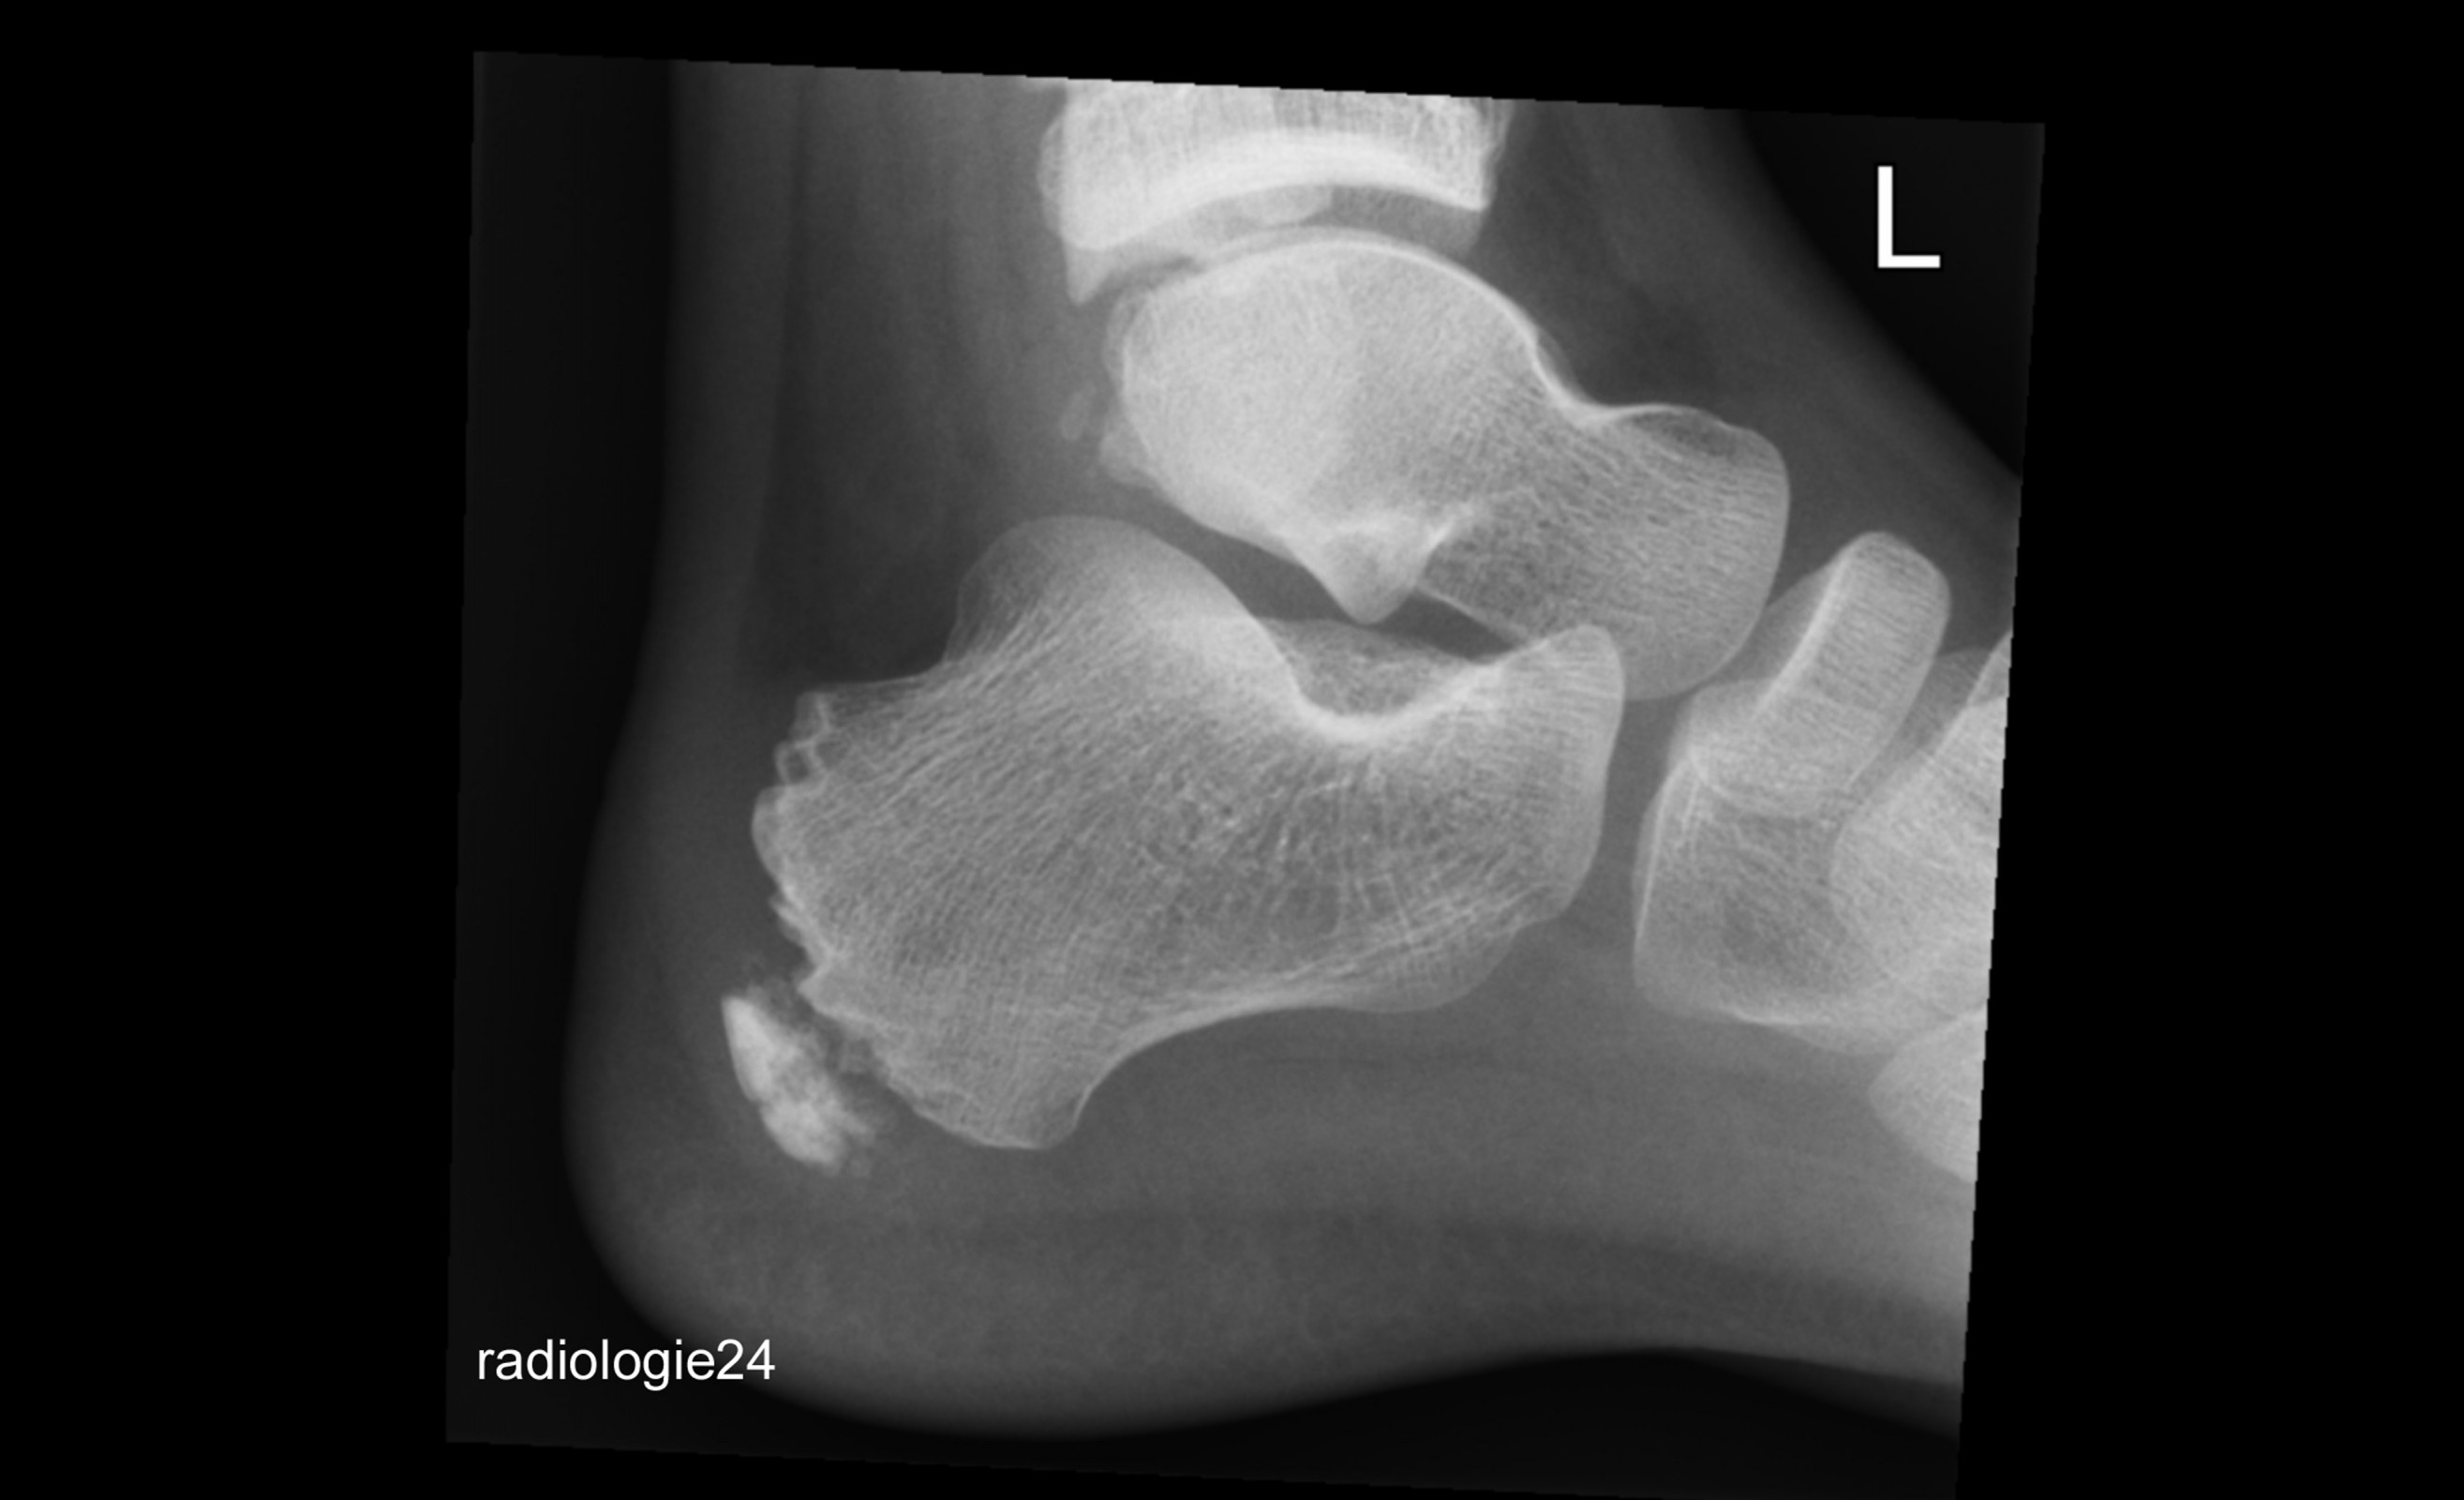

Röntgenfall des Monats April 2018 mit Auflösung

10 jähriger Patient Schmerzen im Bereich des Achillessehnenansatzes nach Fussballspiel. Ihre Diagnose? Weitere Abklärung?

Bild vergrössern